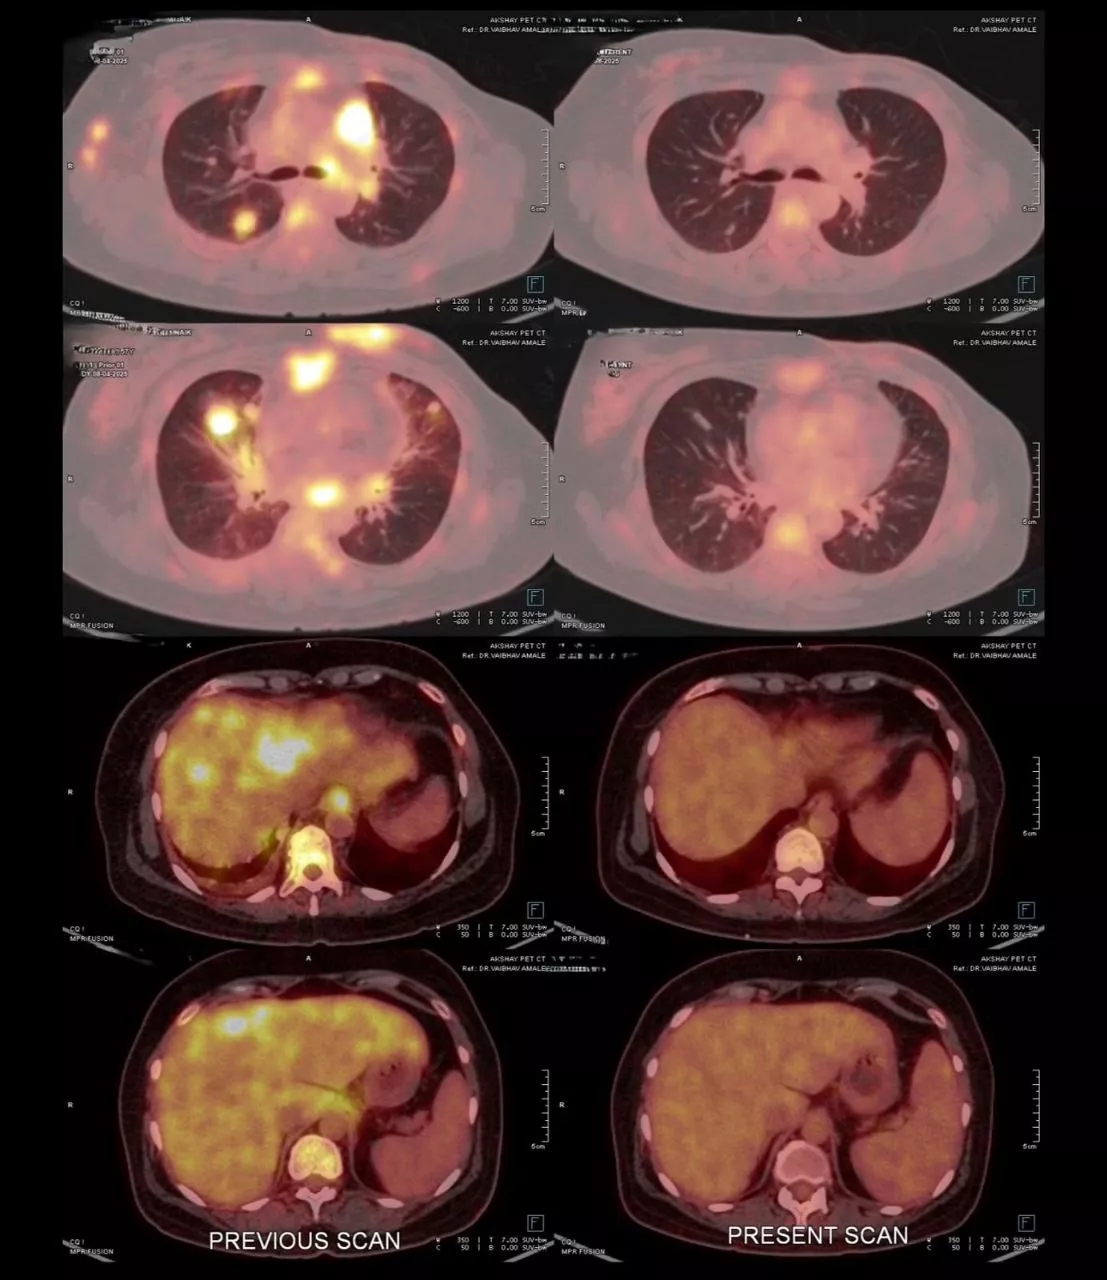

Patient is a 50 year female, Her2 positive metastatic breast cancer. She was diagnosed 2 years back with breast cancer. On diagnosis she was having lung metastatis. She received first line therapy with Paclitaxel and Trastuzumab. After one and half years, she had progression. She received second line treatment with Cap. Lapatinib and Tab. Capecitabine. She responded for 6 months. After 6 months she again progressed with new liver lesions, chest wall lesions and brain lesions. She was symptomatic for brain metastasis- headache, fatigue. She had mild derangement of liver function with elevated SGPT and SGOT, tender hepatomegaly. At this time we treated her with Inj. Trastuzumab Deruxtecan every 21 days. After 1 cycle she showed clinical improvement with reduced headaches and abdominal pain. After 2nd cycle she was almost asymptomatic, LFTs normalised. After 6 cycles, PET scan is showing Complete metabolic response. Brain lesions are metabolically inactive - resolved. She is currently asymptomatic and continuing same treatment.